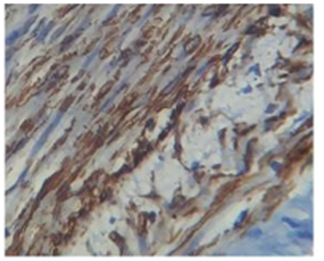

Gutierrez G et al.26 reported incidence of 1.1% of Dermatofibrosarcoma protruberance of all the soft tissue sarcomas and 0.06% of all malignant tumors.50 In the present study they constituted about 3.4% of all the soft tissue sarcomas. Gutierrez G et al.26 reported a male predominance accounting to 36%. Males are more frequently affected as reported by Enzinger FM & Weiss SW. In the present study a Female patient was involved. In a review of 853 cases at AFIP 1960-79 the site distribution was noted to be 14.5% in head and neck, 47.4% in trunk, 18.2% in upper extremities, and 19.9% in lower extremities. In the present study 1 case was noted in the lower extremity, which shows CD34 positivity. Only 1 case of Leiomyosarcomas was encountered in our study, constituting an incidence 3.4% of soft tissue sarcoma. The Location of tumor was Paratesticular region, a rare site in 71years old male patient. Immunohistochemistry shows strong positivity for SMA and Desmin, Moderately positivity for EMA and Vimentin and negative for S100 and Myogenin (Figures 12-14).

Figure 12 LEIOMYOSARCOMA showing SM actin.

Figure 13 Showing DESMIN positivity.

Figure 14 Showing DESMIN positivity.